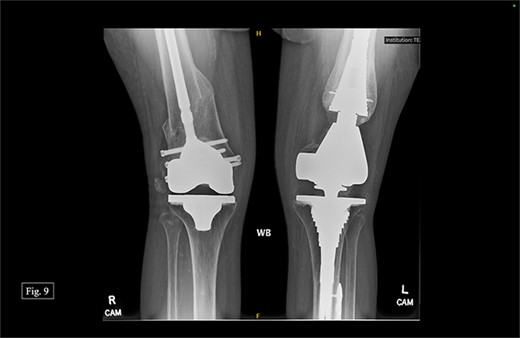

During her most recent visit in February 2024, 17 months post-op on the right, bilateral AP, right & left lateral, right & left AP, and full leg-length X-rays were taken. When looking at the right AP and lateral imaging, she had findings of progressive bone healing, maintained surgical alignment, and all hardware was intact (Fig. 8). Further, when looking at the bilateral AP and full leg length imaging, she had maintained hip alignment, equal leg length, and no changes in valgus or varus leg alignment (Figs 9 and 10). The patient reported a resting right knee pain of 1/10 and an ambulatory right knee pain of 2/10 with a full ROM. She was instructed to continue at-home physical therapy and NSAIDs as needed for pain and to return to the clinic in 6 months for further evaluation.